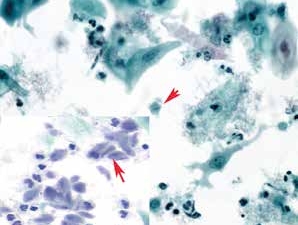

1. 单纯疱疹病毒(herpesvirus simplex)(图2-20~2-24)

图2-20 单纯疱疹病毒(高倍、液基、巴氏染色)

嗜伊红染的核内包涵体(红箭头),形状与其核相似,少见。染色质退变为毛玻璃样(黄箭头)。

图2-21 单纯疱疹病毒(高倍、液基、巴氏染色)

被感染的细胞单核、双核及多核(插图)。核的形态特征:毛玻璃样,拥挤镶嵌,染色质边聚,核膜增厚,有时可见核内包涵体。

图2-22 单纯疱疹病毒(高倍、液基、巴氏染色)

被感染的细胞单核、双核及多核(红箭头)。毛玻璃样核,核膜增厚,胞质少,无核仁。炎细胞较多。插图嗜伊红染的核内包涵体,偶见。

图2-23 单纯疱疹病毒(高倍、液基、巴氏染色)

被感染细胞多核,拥挤镶嵌,毛玻璃样染色质,染色质聚集在核膜下使核膜增厚,嗜碱性染色。背景炎细胞较多。

图2-24 单纯疱疹病毒(高倍、涂片、巴氏染色)

被感染细胞典型的核改变:多核、核塑形、染色质边缘化。炎性背景明显。

细胞形态特征:被感染的细胞表现为多核伴有胞核增大,胞核拥挤镶嵌,毛玻璃样染色质,染色质聚集在核膜下而使核膜增厚,多呈嗜碱性。典型病变细胞特征为:多核、核塑形、染色质边缘化。偶见嗜伊红染色的核内包涵体,形状与其核相似。背景有较明显的急性炎性改变。

疱疹病毒感染不成熟的鳞状上皮细胞、化生细胞以及子宫颈管腺细胞。病毒主要侵犯细胞核,细胞核的变化是诊断的关键。需要注意宫颈细胞学并不是诊断HSV感染最可靠的方法,PCR检测方法相对更敏感和快速。鉴别:炎性的多核柱状上皮、化生细胞、多核巨噬细胞。